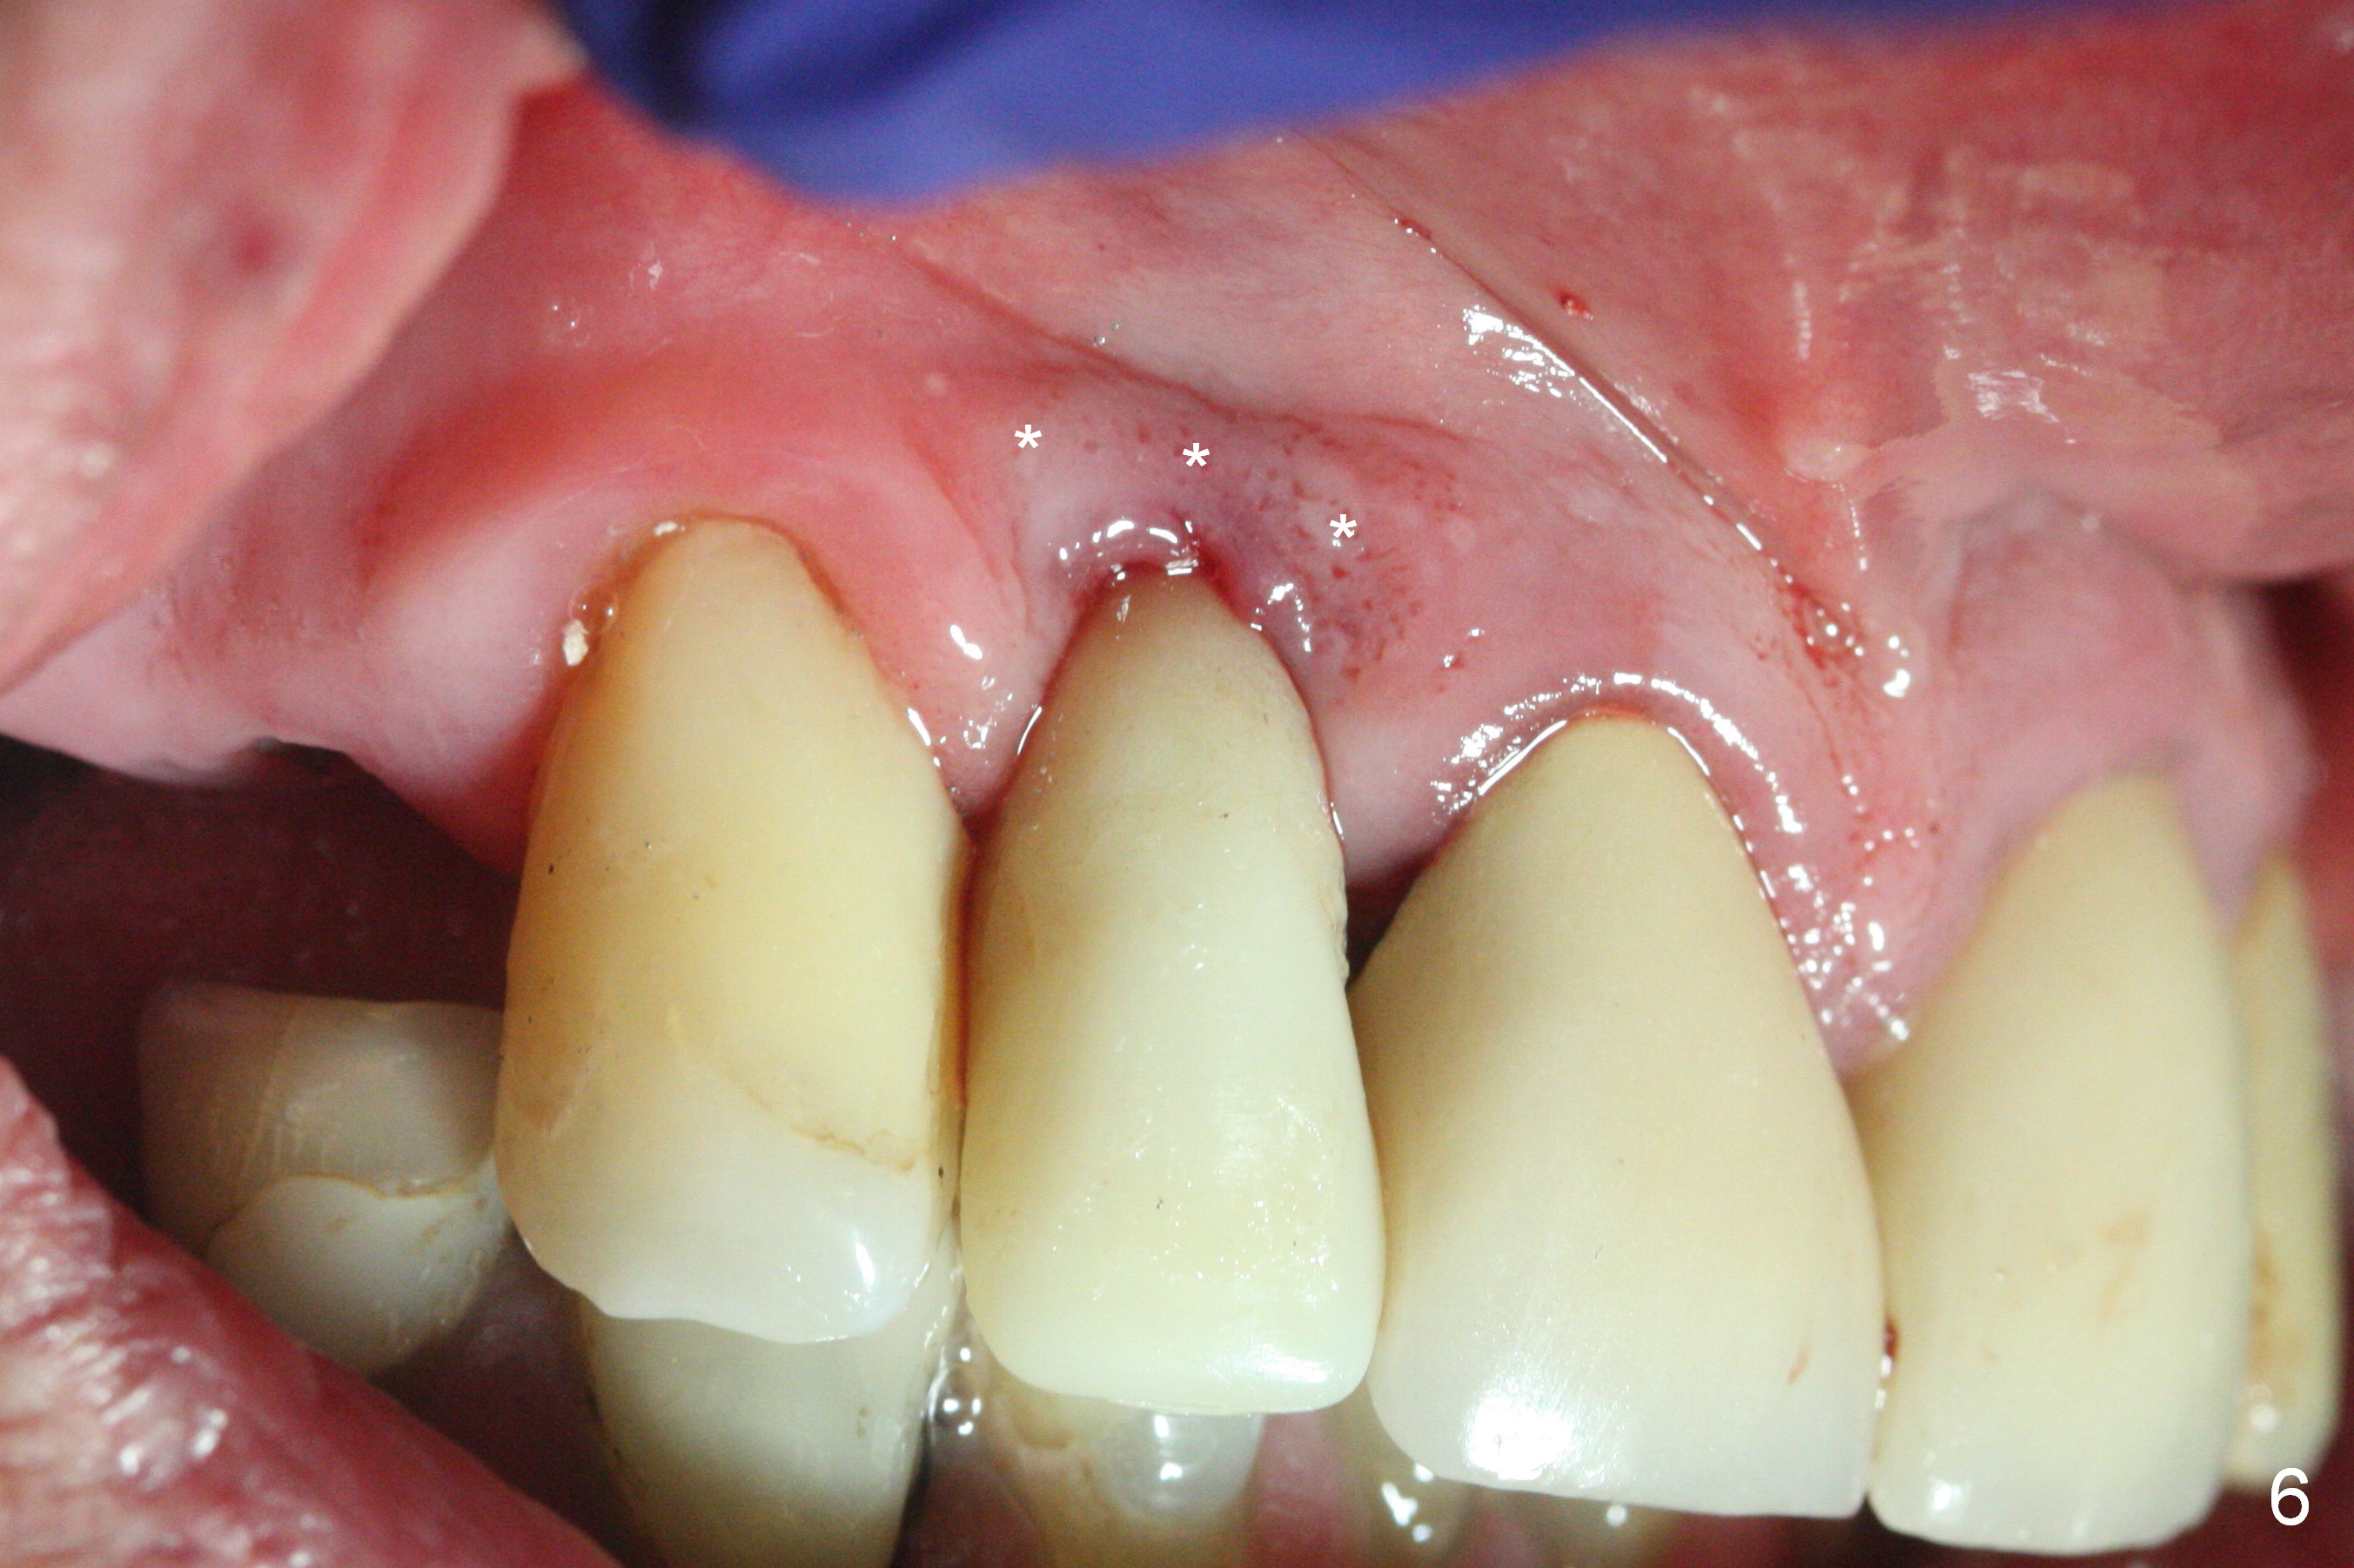

The residual root at #7 is fairly well exposed with buccal gingival recession (Fig.1). The implant placement is flapless (Fig.2-7). What is not shown is that the 3.8x13 mm implant is buccally subcrestally placed (Fig.3). After 1st round of bone graft buccal to the implant, a 4.5x5(5) mm abutment is immediately placed and prepared (Fig.4,5). An immediate provisional is placed after 2nd round of bone graft subgingivally buccally (Fig.6,7). Note the bulging gingiva (*), as compared to that in Fig.4,5. The long implant is chosen because of anterior deep bite (Fig.4) and lack of posterior support (Fig.7).